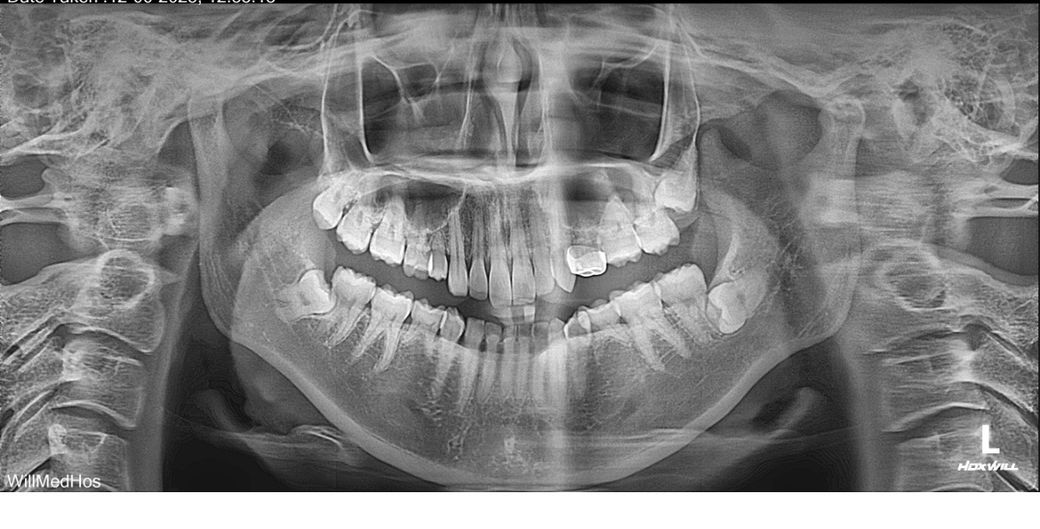

사랑니 발치해야 하나요? ㅠㅠ 봐주세요!!!

저는 영구치 결손이 6개 정도 있어요.

이런 상황에서도 사랑니를 꼭 발치해야 하는지 궁금해서 파노라마를 찍고, 그 뒤에 CT까지 찍어봤어요.

혹시 파노라마는 왼쪽에 보이는 치아가 실제로는 오른쪽 치아 맞나요?

아랫니 사랑니들은 누워 있어서 발치해야 한다는 건 이해했는데,

오른쪽 윗사랑니는 그나마 일자로 난 것 같아 보이는데 이것도 꼭 빼야 하는 걸까요?

영구치 결손이 있어서 “나중에 대체 치아처럼 쓰일 수 있을까?” 싶었는데, 그런 사용도 불가능한 건지… 궁금해요.

그리고 제가 찍은 사진 속 사랑니들은 모두 매복 맞나요?

1. 오른쪽 위 사랑니는 관리만 잘 된다면 안빼도 될 것 같습니다. 매복 아닙니다. 나머지는 매복입니다.

2. 어차피 매복 사랑니는 자가치아이식으로 쓰기 어렵습니다 발치 할 때 치아를 쪼개서 뽑거든요. 그런 기대를 가지고 사랑니 발치를 안하는 건 말이 안됩니다.